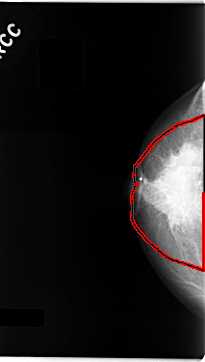

FILE: C_0061_1.RIGHT_CC.OVERLAY

TOTAL_ABNORMALITIES 1

ABNORMALITY 1

LESION_TYPE MASS SHAPE IRREGULAR MARGINS SPICULATED

ASSESSMENT 5

SUBTLETY 5

PATHOLOGY MALIGNANT

TOTAL_OUTLINES 1

BOUNDARY